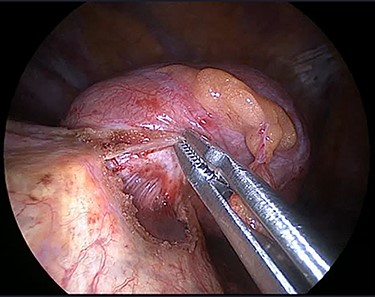

The operation was performed under general anaesthesia with the patient intubated using a double-lumen endotracheal tube. A 4 cm incision was made in the right sixth intercostal space in order to locate the mass. After the insertion of a 10 mm 30-degree thoracoscope, a rounded smooth-surfaced, broad necked mass attached to the right hemidiaphragm was visualized (Fig. 3). The decision to open the diaphragm was made. Further dissection and exploration with an energy device revealed that the mass which was bounded superiorly in the form of a pouch by the diaphragm and had arisen from the liver (Fig. 4). The mass was completely resected with HARMONIC ACE® +7 (Ethicon) after consulting with the hepatobiliary surgeon who felt there was a clear cleavage plane between the mass and liver. The exposed area of liver was covered with Floseal®(Baxter) and TachoSil®(Takeda). The diaphragmatic defect (Fig. 5) was closed in a single layer with 10 simple interrupted silk sutures (Fig. 6). The remainder of the surgery was uncomplicated, and the patient was discharged home on the second postoperative day. Subsequent histology findings reported the mass as benign (accessory) hepatic tissue (Fig. 7).

Diaphragmatic defect was closed in a single layer with simple interrupted stitches.